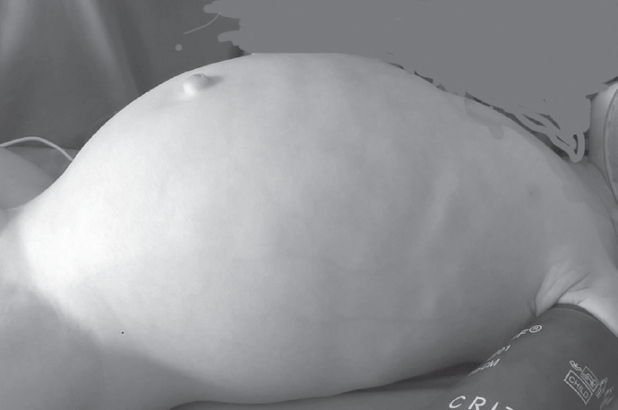

Hirschsprung’s disease usually manifests from the first days of life and is diagnosed in the newborn period. In some patients Hirschsprung’s disease can’t be diagnosed in the newborn period because of different forms of disease and clinical features. From 2008 to 2019 75 patients with Hirschsprung’s disease were operated in the City Children’s Hospital No. 1. 21 patients had delayed diagnosis. 11 newborns didn’t have very clear clinical symptoms, intestinal obstruction disappeared after decompression. 2 patients with associated chromosomal disorders were diagnosed with Hirschsprung’s disease later because of. In some of older patients disease manifested with severe constipations. Also, we presented some clinical cases of major diagnostic errors in patients with Hirschsprung’s disease. Conclusion. Diagnostic errors in patients with Hirschsprung’s disease are associated with the lack of alertness of neonatologists and inadequate interpretation of clinical manifestations and X-ray study. For many years these children can be treated by different specialists before having surgical consult.